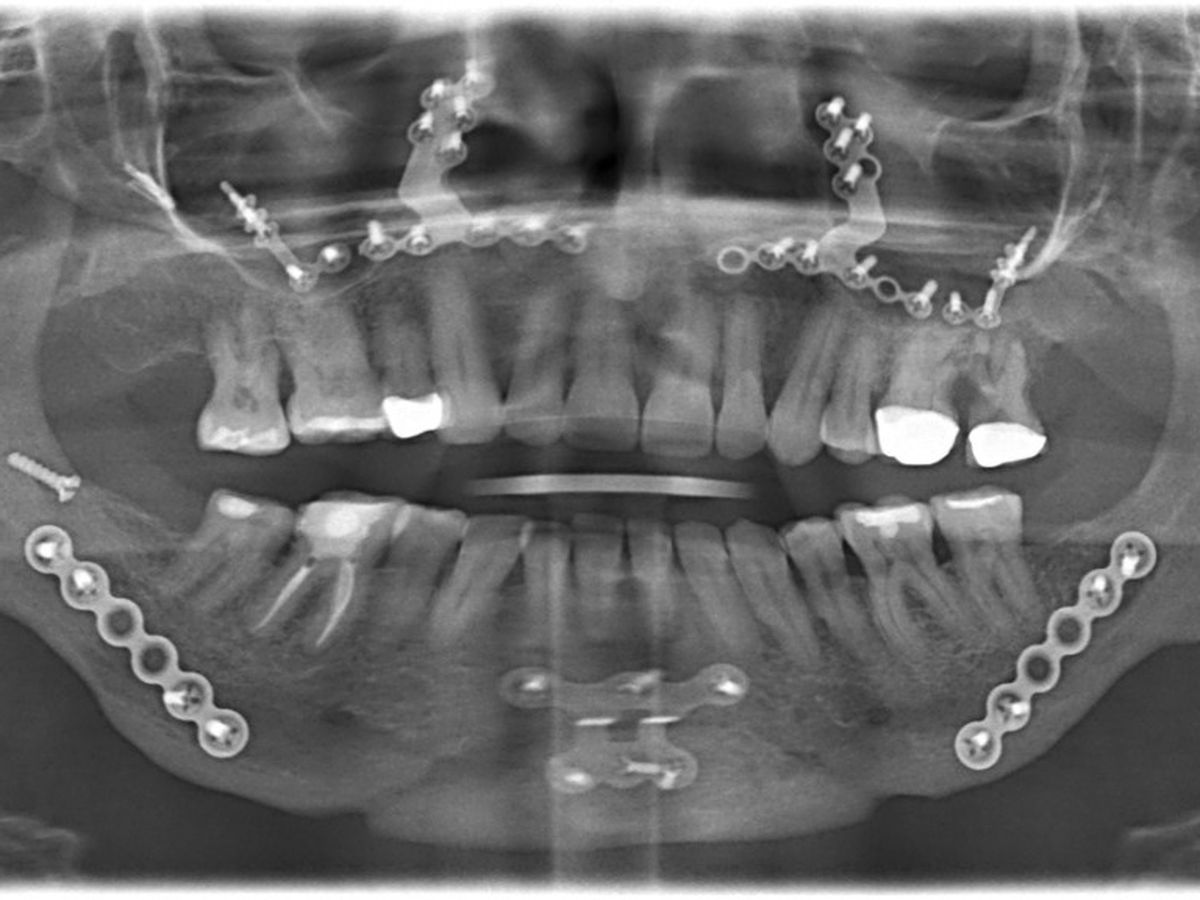

I had double jaw surgery (DJS) on 1/23/20 to correct my sleep apnea. As you can see from the X-ray, there is lots of hardware in my face. That plate on my chin is causing my jaw bone to be infected and eaten away. I need surgery in Boston to remove the chin plate, clear out the infection, perform a bone and gum graft, do a corrective DJS, extract my lower front teeth, get a partial or bridge, and have a rhinoplasty done.

I had double jaw surgery (DJS) on 1/23/20 to correct my sleep apnea. As you can see from the X-ray, there is lots of hardware in my face. That plate on my chin is causing my jaw bone to be infected and eaten away. I need surgery in Boston to remove the chin plate, clear out the infection, perform a bone and gum graft, do a corrective DJS, extract my lower front teeth, get a partial or bridge, and have a rhinoplasty done.